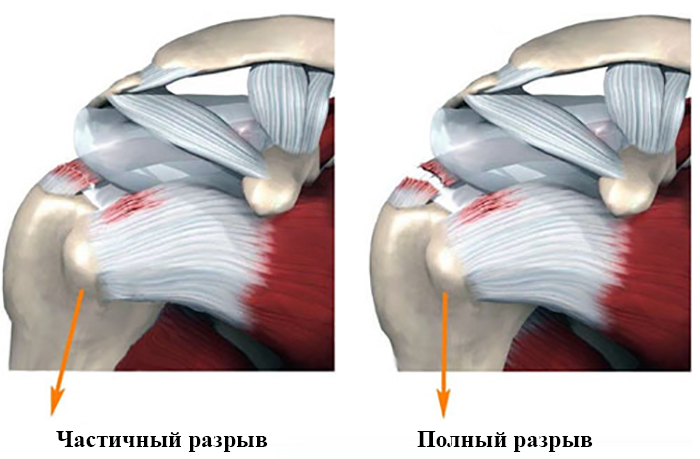

Фотографии мышц ротаторной манжеты плеча